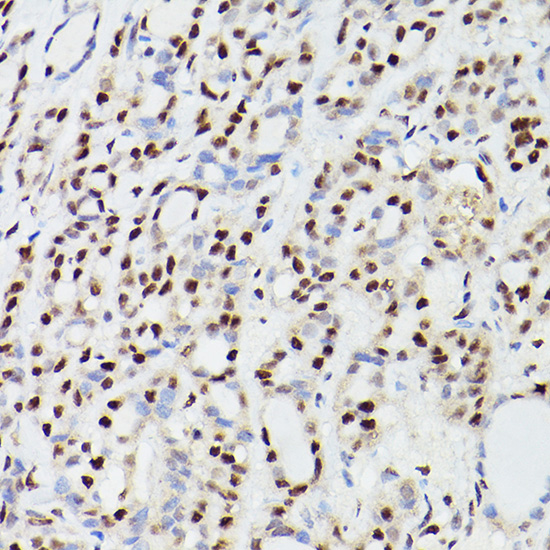

Immunohistochemistry of paraffin-embedded human esophageal cancer using CPSF6 Rabbit pAb.

Immunohistochemistry of paraffin-embedded human thyroid cancer using CPSF6 Rabbit pAb.

Immunohistochemistry of paraffin-embedded mouse lung using CPSF6 Rabbit pAb.

Immunohistochemistry of paraffin-embedded rat testis using CPSF6 Rabbit pAb.